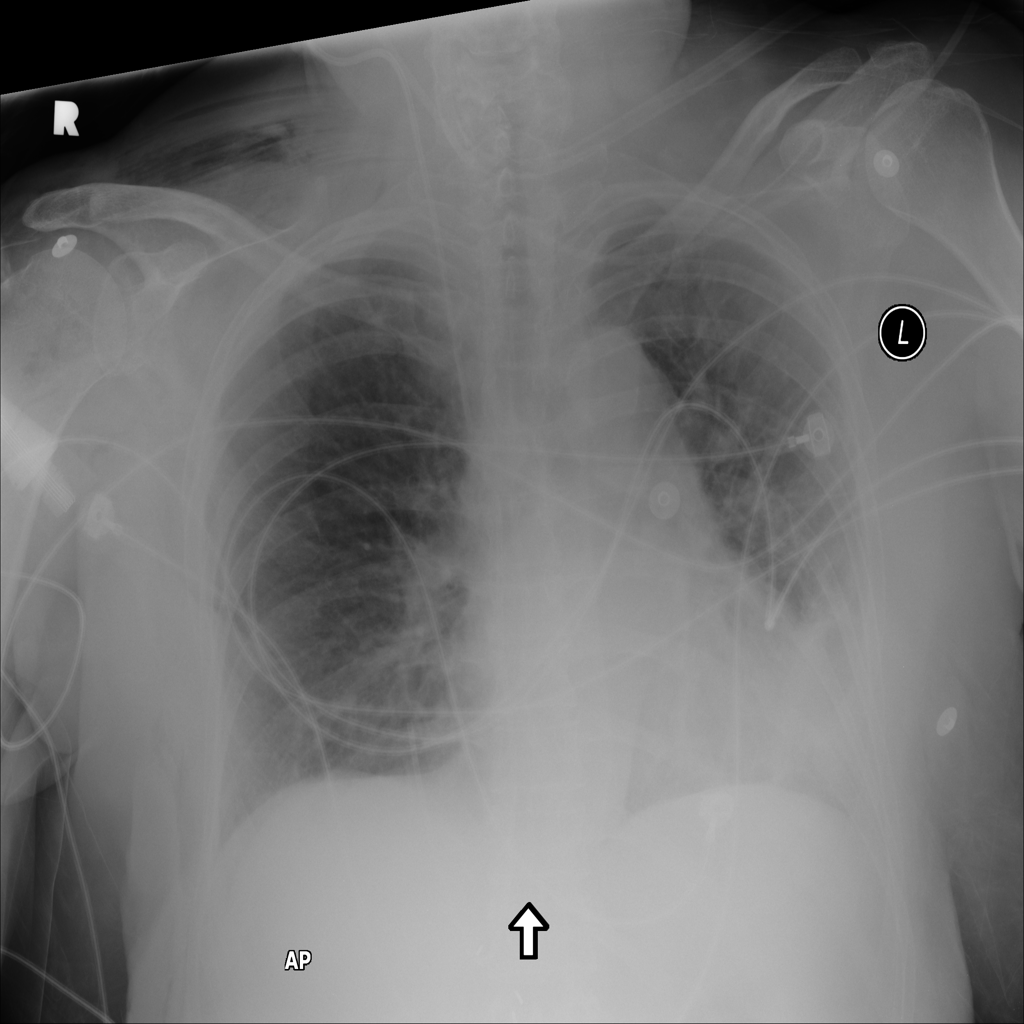

PAT-E828 · IMG-005Edema

PAT-E828 · IMG-005

AP